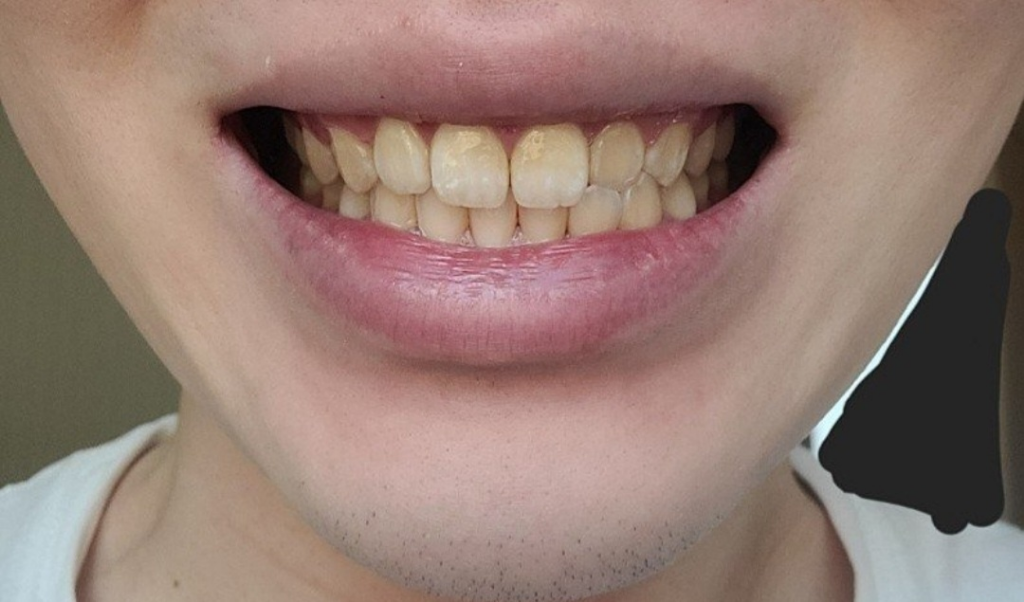

당연히 치아를 꽉 깨물고 있으면 불편감이 잇습니다. 치과 악습관중에 이꽉깨물기 이갈이등이 있습니다. 앞니 교합이 긴밀하신거 같긴합니ㅏㄷ.